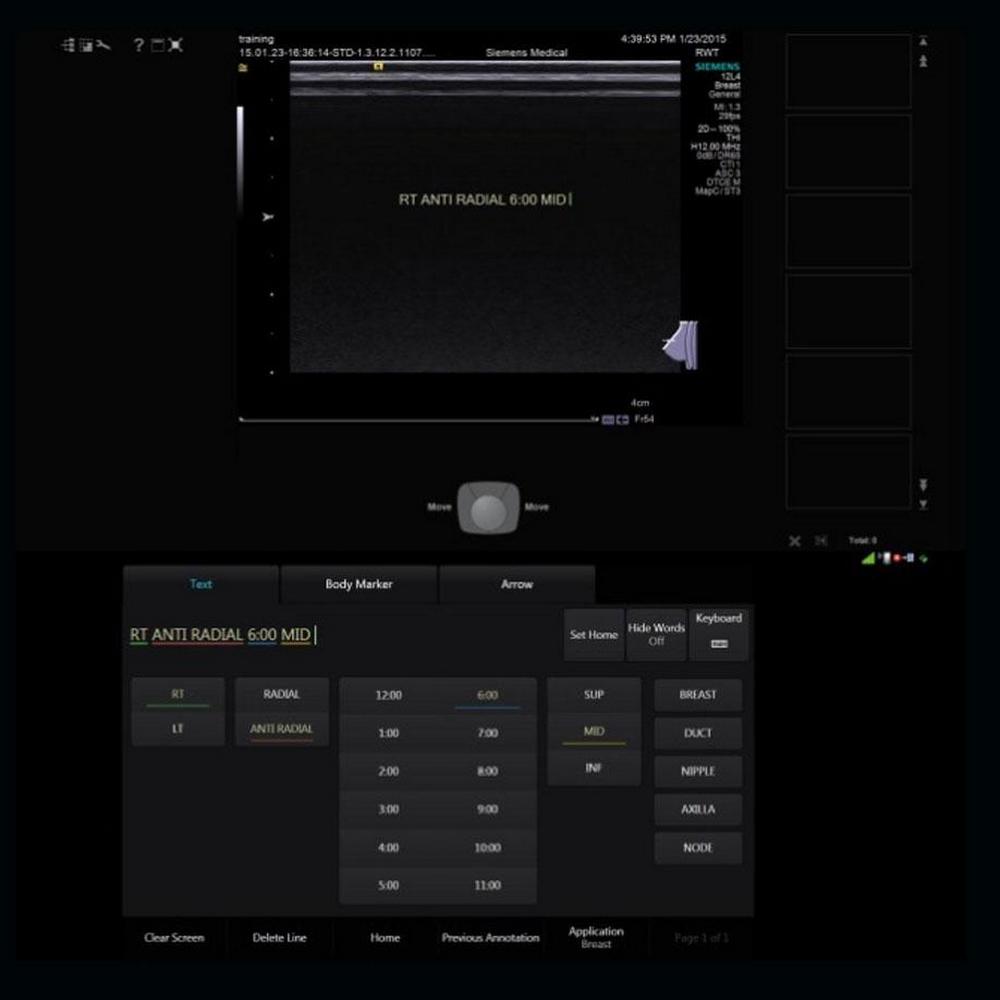

- Сенсорный экран с диагональю 12,1 дюйма и технологией мгновенного отклика Instant Response обеспечивает высокую точность выбора элементов управления.

- Интерфейс на основе вкладок и папок не содержит скрытых меню и обеспечивает удобную навигацию без лишних перемещений пальцев по экрану.

- Четкие и понятные изображения анатомических структур, маркеры датчиков и удобные обозначения программ исследований.

- Технология Smart-swap с цветовой кодировкой упрощает ввод аннотаций, предлагая врачу УЗД текстовые подсказки, соответствующие проводимому исследованию.

- Прямой доступ к рабочим протоколам eSieScan™ через интерфейс сенсорного экрана.